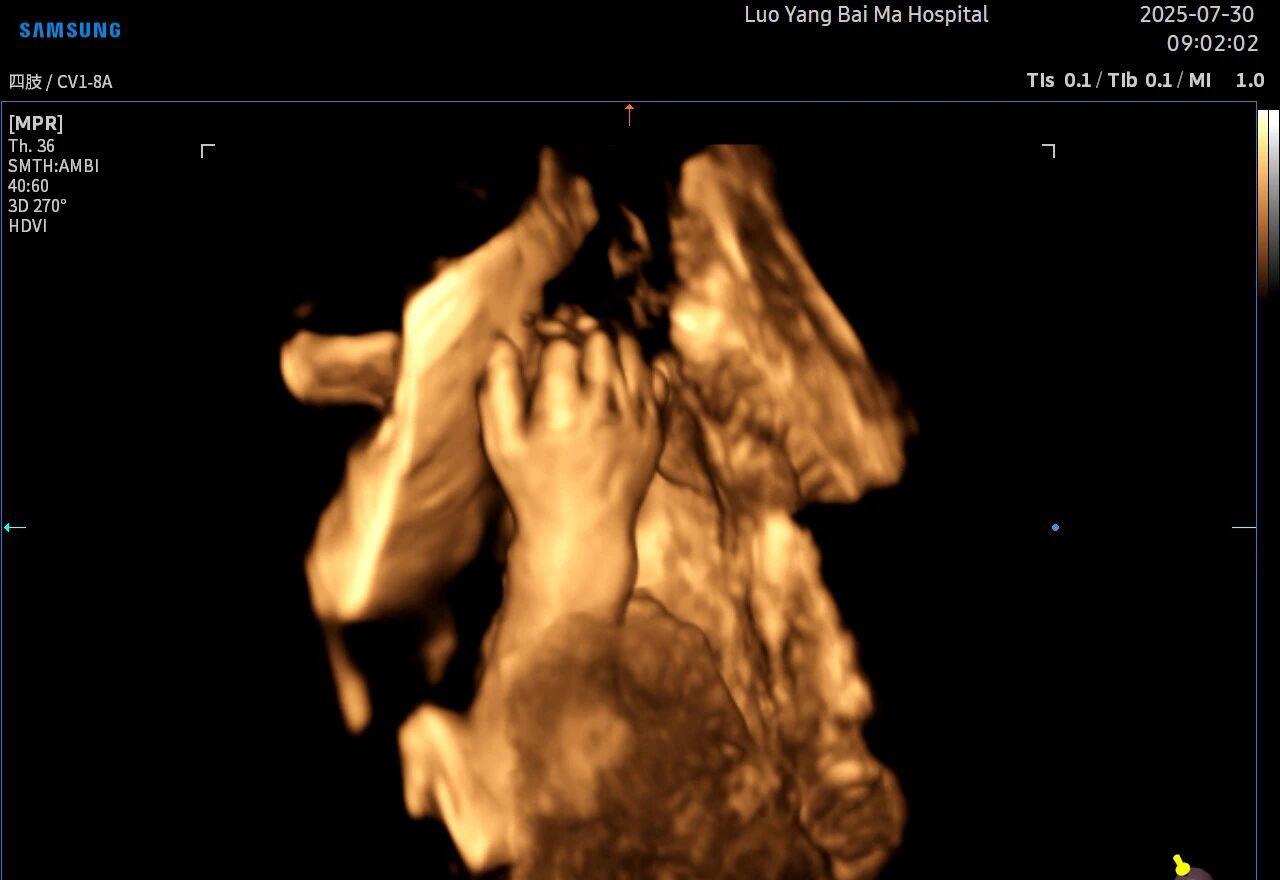

很多准妈妈可能对四维(4D)彩超已经非常熟悉,它能够实时动态地展示宝宝在宫内的活动,让我们看到宝宝打哈欠、伸懒腰的可爱模样,为无数家庭留下了珍贵的第一份“动态影集”。

2. 全方位、多角度的“360度”观察

传统超声检查有时会因为胎儿体位、羊水量等因素的限制,导致某些部位观察不清。5D智能彩超技术能够实现对目标结构进行360°全方位、多切面的自由旋转观察。医生可以像“雕塑家”一样,从任意角度审视胎儿的解剖结构,尤其对于形态复杂的心脏、颅脑和脊柱等部位,这种能力可以极大弥补单一平面的局限性,帮助医生更全面地评估其发育状况。